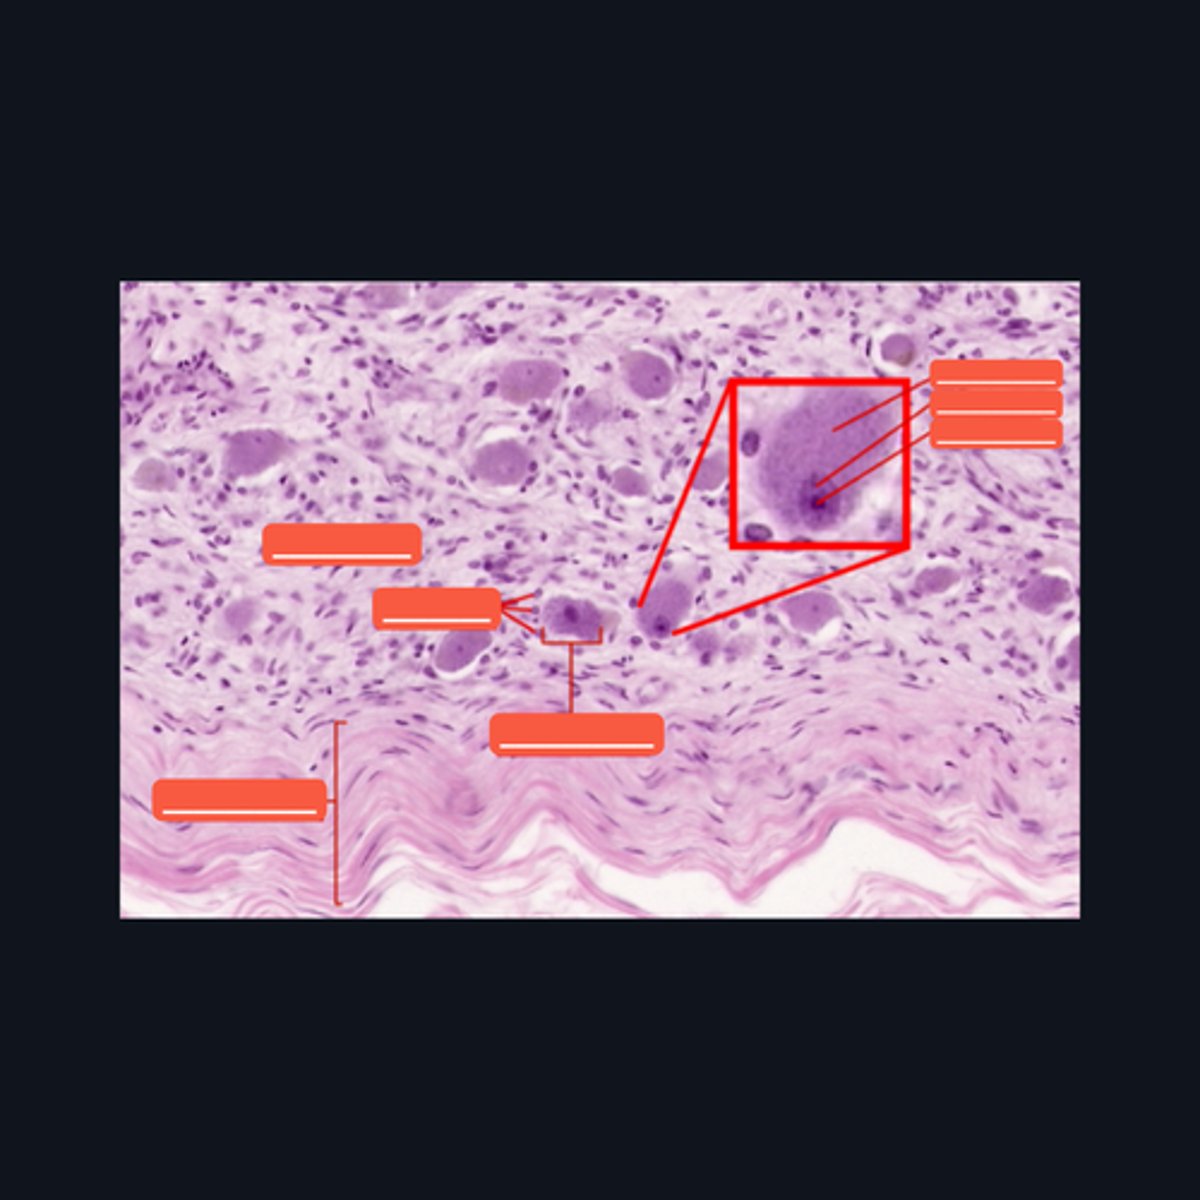

Dorsal root ganglion and nervous tissue

Identify the specific structure given in the image, as well as the type of tissue predominating in the structure.

(top to bottom)

Somatic sensory neurons

Capsule

Identify the structures of the dorsal root ganglion. Be as specific as possible.

(top to bottom)

Cell body

Satellite cell

Nucleus

Nucleolus

Nerve fibers

Identify the parts of the spinal ganglion in high magnification.

False, pseudounipolar

T or F: The neurons that congregate in this structure is multipolar.

(bottom to top)

Capsule

Ganglion Cell

Satellite cell

Nerve fibers

Nucleolus

Nucleus

Nissl Granules

Identify the structures of a sympathetic ganglion.

Multipolar, autonomic motor neurons

What kind of motor neurons are present in this structure?

Dense Irregular Connective Tissue

What kind of tissue is the capsule of a spinal ganglion made up of? Be specific.